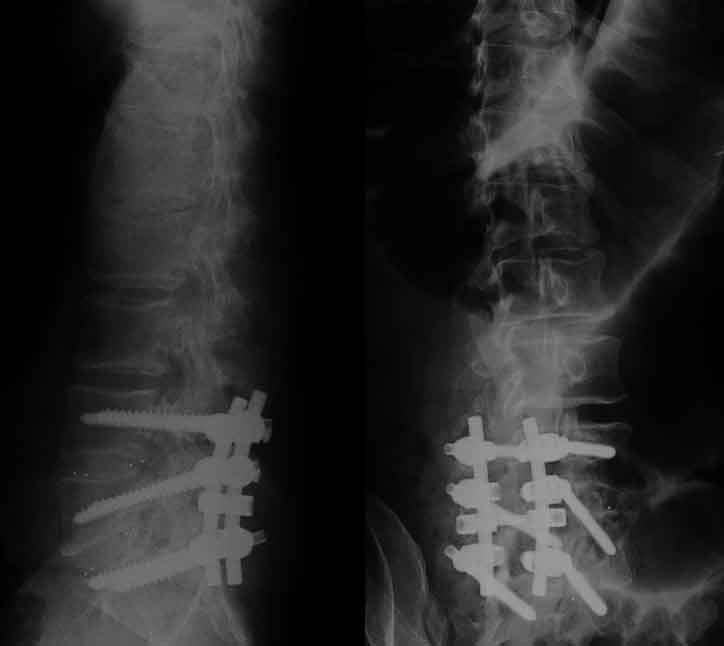

This is an X-ray of Ken's Lumbar Spine Taken in October of 2020

It shows 6 screws & 3 rods. The tiny dots are from the 4 cages

2 on each level The Dark Sideways Mushroom Looking Shadows

Above the Top Screws, Show the Damage Caused from Years of

Stress to that area and Explain why He has so much Pain